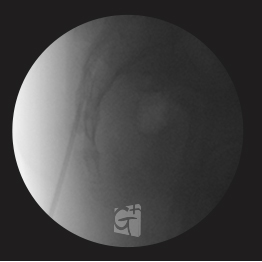

경추 선택적 신경치료

경추 6번에서 시행된 선택적 신경치료 약물이 신경근과 추간공 안쪽으로 잘 퍼지는 모습